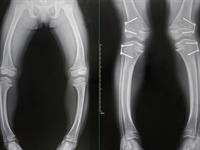

4. Rahīts ir deformēta krūškurvja forma, kā arī kāju deformācija – tās ir vai nu ceļgalos izliektas uz āru (O veida), vai arī ceļgalos ieliektas uz iekšu (X veida). Veidojas bērnībā, ja organismā ir D vitamīna un kalcija trūkums.